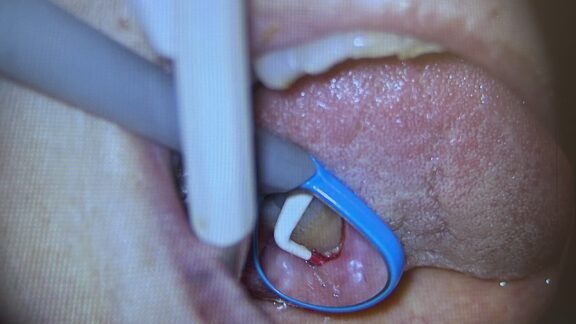

下の写真は、実際にマイクロスコープを使用して 歯周ポケットを測定している場面です。

プローブ(細い器具)を歯と歯ぐきの間に挿入し深さをミリ単位で測定します。

◎拡大視野で確認

肉眼では見えにくい歯石や炎症の状態を、マイクロスコープで細かくチェックできます。

◎出血の有無も確認

測定時に出血が見られる場合は、炎症が起きているサインです。

🔼この部分を中心に丁寧なクリーニングや治療を行います。